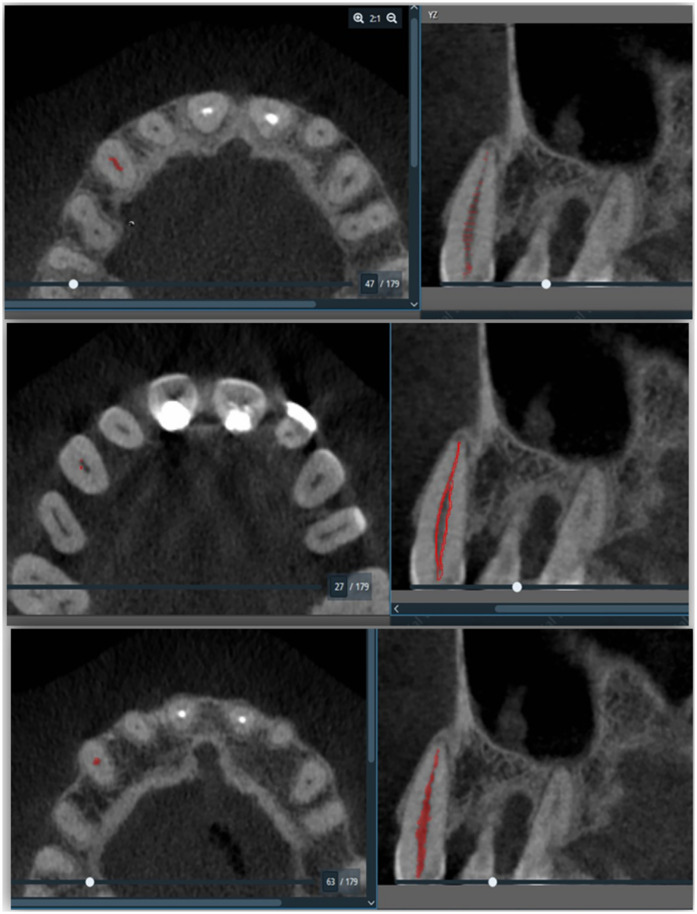

Objective: The objective for this study was to establish a correlation between pulp volume and periodontal disease using Cone-Beam Computed Tomography (CBCT) imaging.

Methods: A cross-sectional study design was employed for the collected data from 148 patients aged 39.51 years using dental images obtained by CBCT and analyzed by medical software to create three-dimensional (3D) images. Pulp-volume analysis was performed using Amira software and measurements were derived using bio-models generated from CBCT images. Obtained data was analyzed using SPSS-27 statistical software.